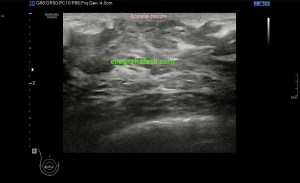

4

Medidas en eje largo